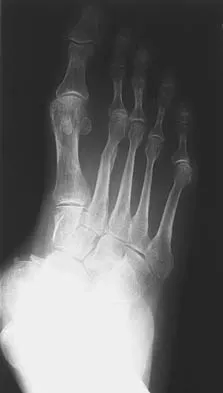

Figures 33a and 33b show the radiographs of a 10-year-old girl who reports a 4-month history of medial foot pain after she was kicked while playing soccer. The pain is worse with activity and partially relieved by rest. Examination reveals tenderness directly over a prominent navicular tuberosity. Management should consist of

Explanation

An accessory tarsal navicular is located at the medial tuberosity of the navicular bone. Nearly all children and adolescents who have a symptomatic accessory tarsal navicular bone become asymptomatic when they reach skeletal maturity. Initial management should include activity restrictions, shoe modification to avoid pressure over the prominent navicular, and non-narcotic analgesics. Although anecdotal, the use of arch supports may be helpful. When pain is refractory to these methods, a short period of cast immobilization may be useful. Surgery should be reserved for patients who have disabling symptoms despite a prolonged period of nonsurgical management. When surgery is indicated, simple excision of the accessory navicular is recommended. Sella EJ, Lawson JP, Ogden JA: The accessory navicular synchondrosis. Clin Orthop 1986;209:280-285.